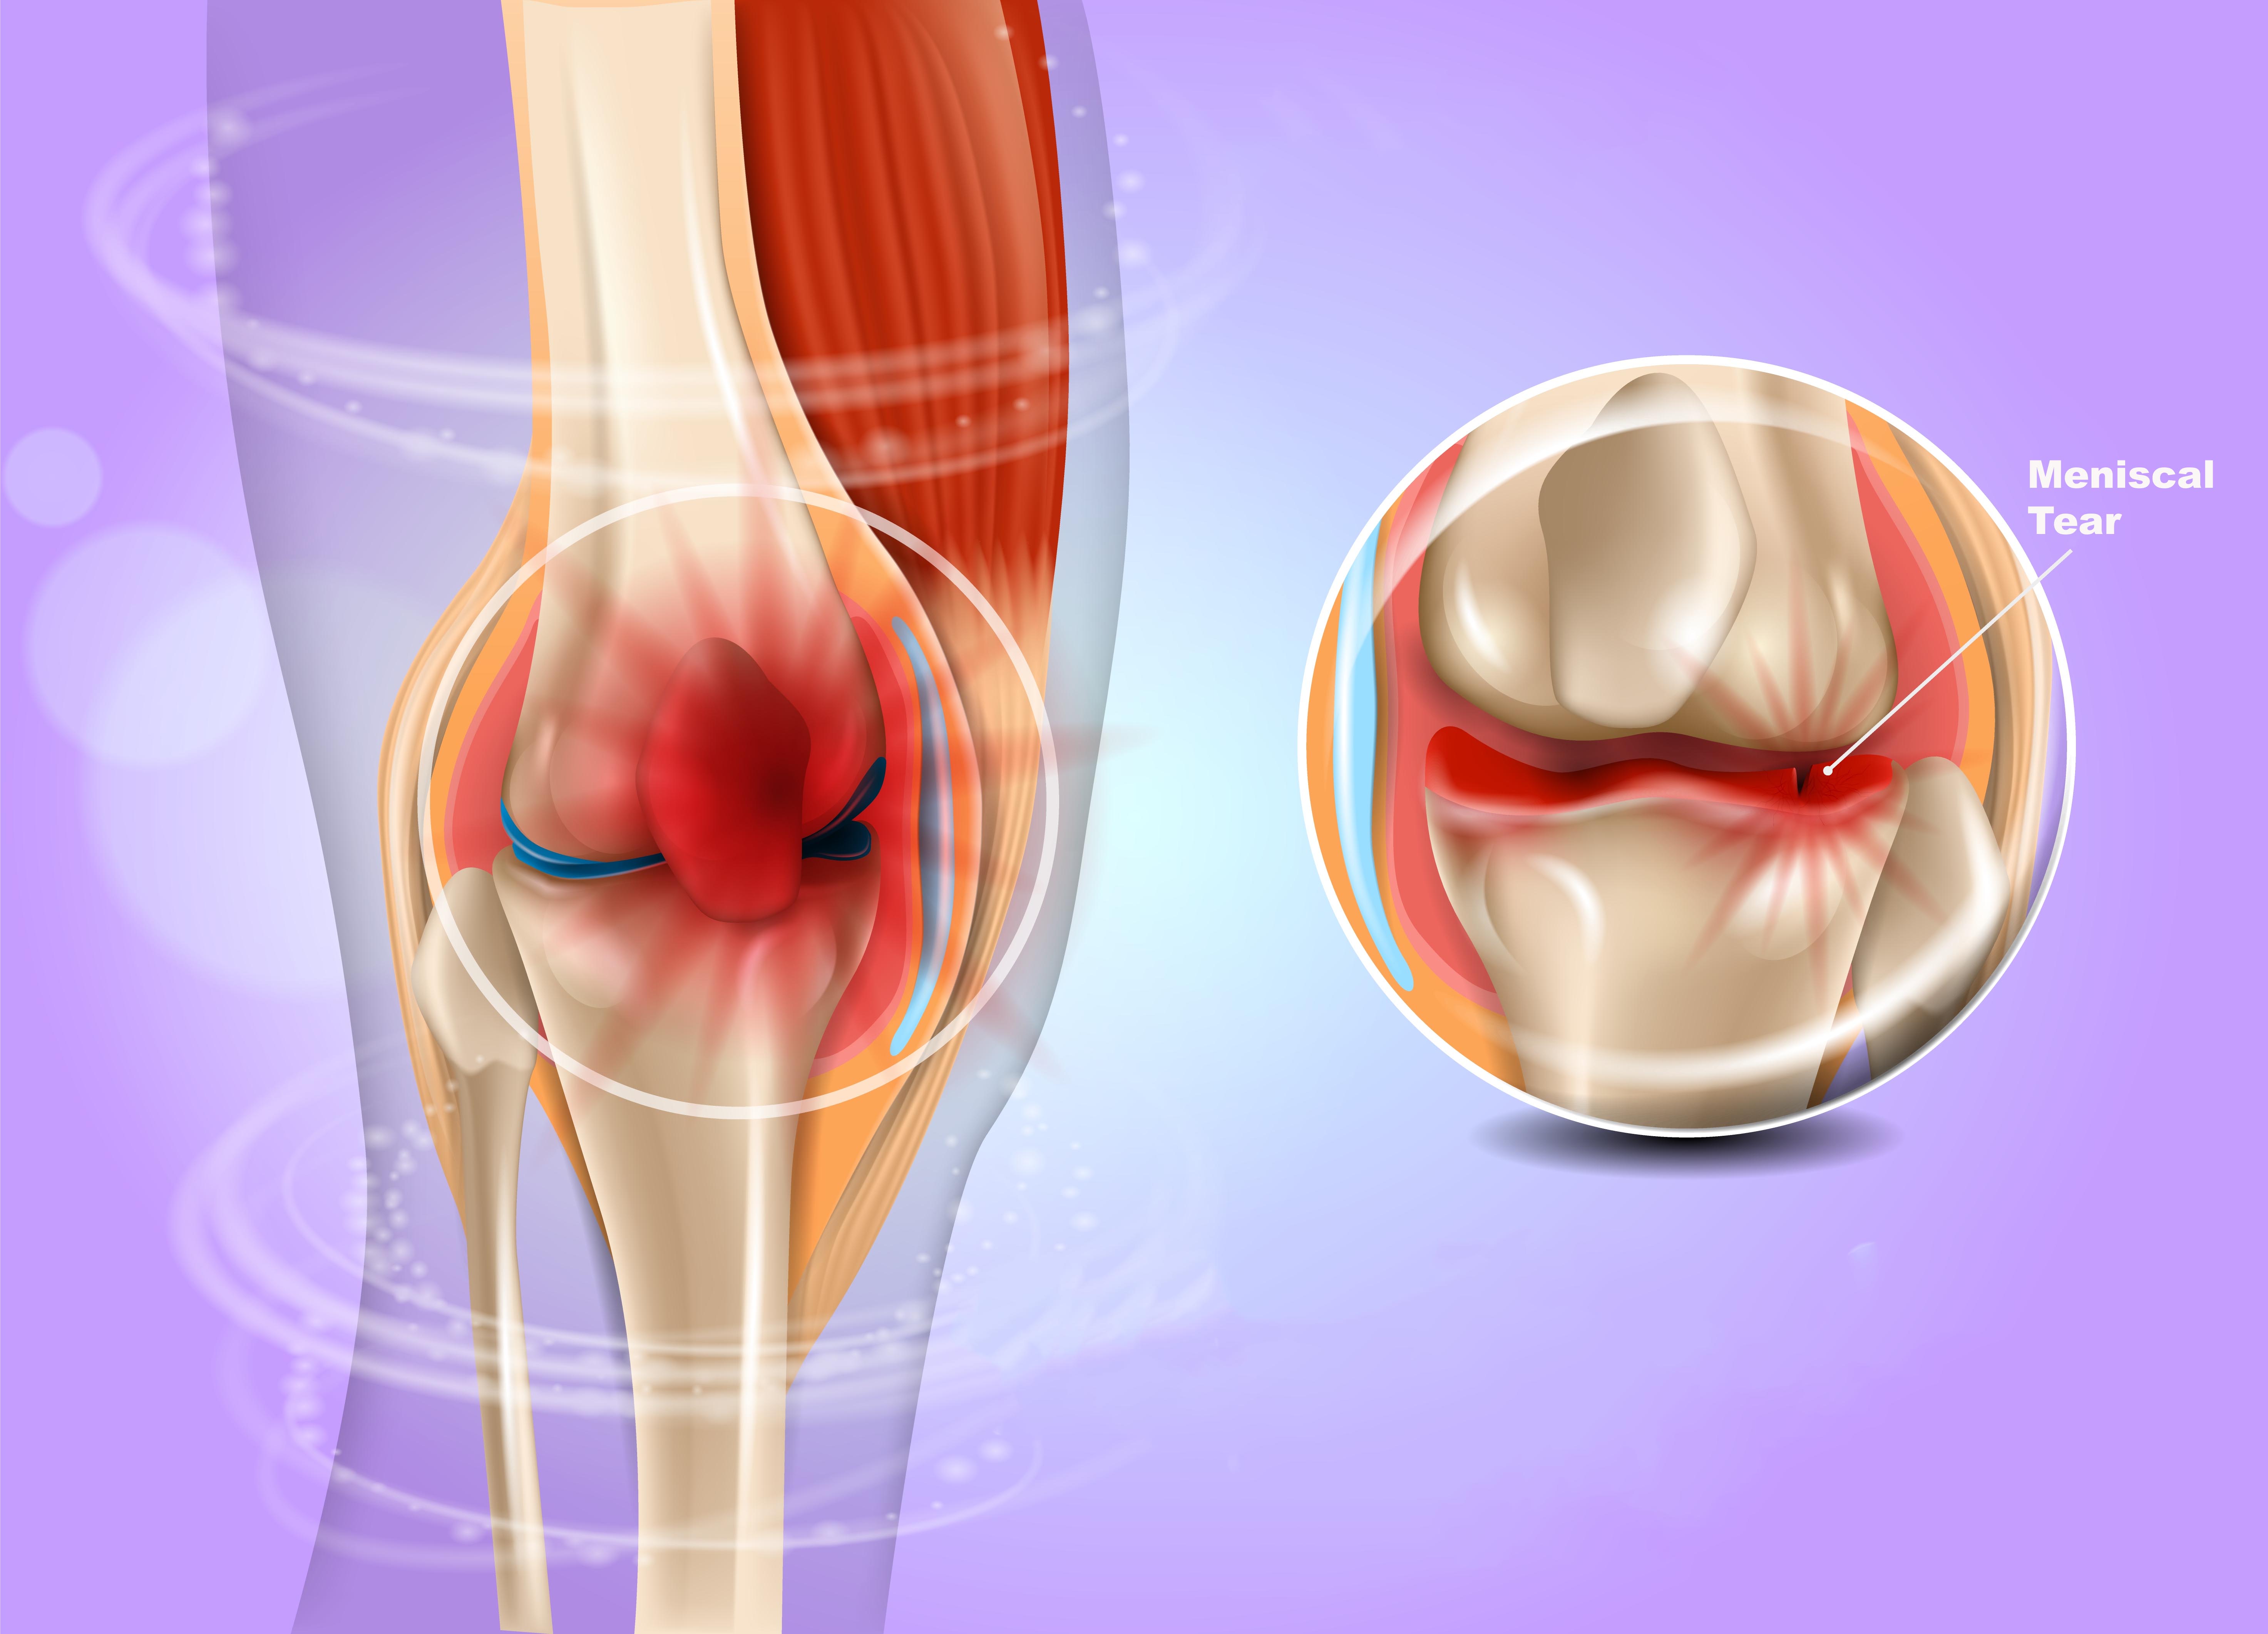

349. Meniscal Tears

By the end of this episode, you will be able to: Recognize the clinical presentation of meniscal injury on history and physical exam. Describe the anatomy of the menisci and classification of tears. Describe operative and non-operative management options for meniscal tears, including the indications, risks, and benefits of each.